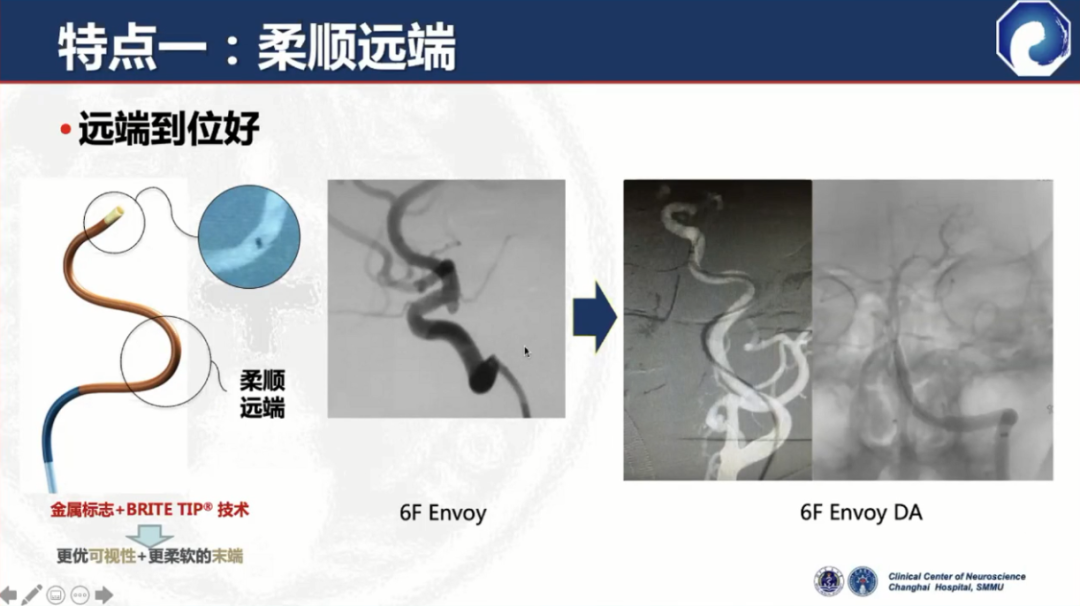

远端柔顺,可达海绵窦段